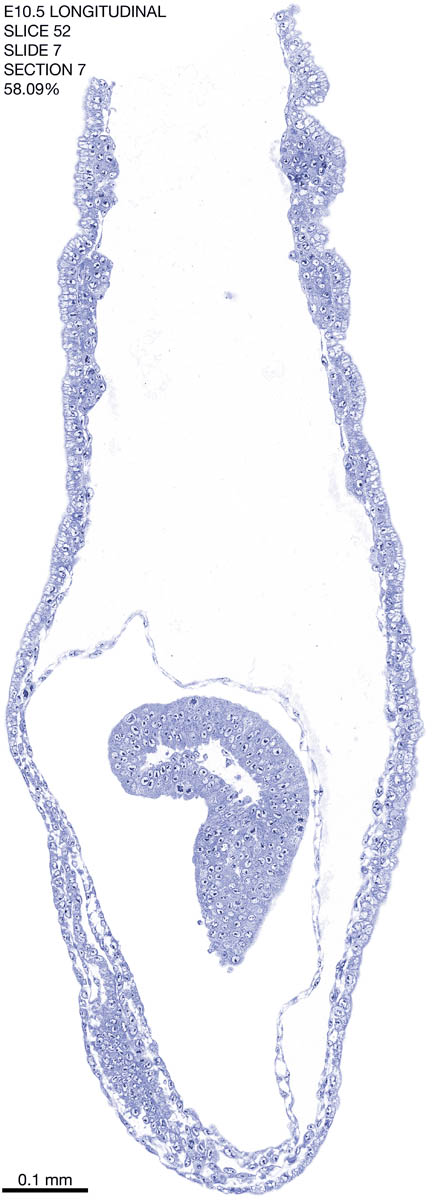

E10.5 Longitudianal Archive This page contains jpg files of ALL SLICES (each 3µm thick) that were scanned of the E10.5 longitudinally cut specimen. Download: Large | High Res Download: Large | High Res Download: Large | High Res Download: Large | High Res Download: Large | High Res Download: Large | High Res Download: Large | High Res Download: Large | High Res Download: Large | High Res Download: Large | High Res Download: Large | High Res Download: Large | High Res Download: Large | High Res Download: Large | High Res Download: Large | High Res Download: Large | High Res Download: Large | High Res Download: Large | High Res Download: Large | High Res Download: Large | High Res Download: Large | High Res Download: Large | High Res Download: Large | High Res Download: Large | High Res Download: Large | High Res Download: Large | High Res Download: Large | High Res Download: Large | High Res Download: Large | High Res Download: Large | High Res Download: Large | High Res Download: Large | High Res Download: Large | High Res Download: Large | High Res Download: Large | High Res Download: Large | High Res Download: Large | High Res Download: Large | High Res Download: Large | High Res Download: Large | High Res Download: Large | High Res Download: Large | High Res Download: Large | High Res Download: Large | High Res Download: Large | High Res Download: Large | High Res Download: Large | High Res Download: Large | High Res Download: Large | High Res Download: Large | High Res Download: Large | High Res Download: Large | High Res Download: Large | High Res Download: Large | High Res Download: Large | High Res Download: Large | High Res Download: Large | High Res Download: Large | High Res